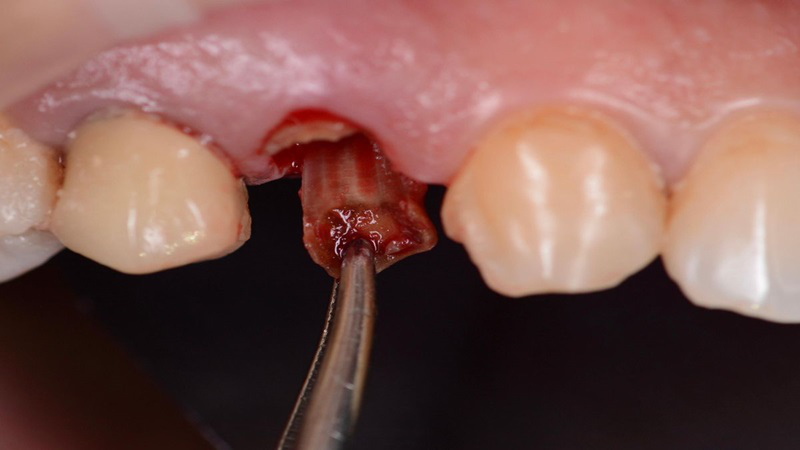

Nhổ sót

Hiện tượng sót chân răng có thể xảy ra trong quá trình nhổ răng. Đặc biệt là khi thực hiện các ca nhổ răng sâu, nhổ răng khôn mọc lệch. Hoặc nhổ răng thừa trong quá trình chuẩn bị niềng răng. Đây là tình trạng có thể xảy ra nếu bác sĩ nha khoa thực hiện không đúng kỹ thuật. Ngoài ra là ca can thiệp gặp phải những khó khăn đặc biệt. Việc sót chân răng có thể ảnh hưởng đến quá trình lành thương. Vì thế cần được xử lý kịp thời để tránh biến chứng.